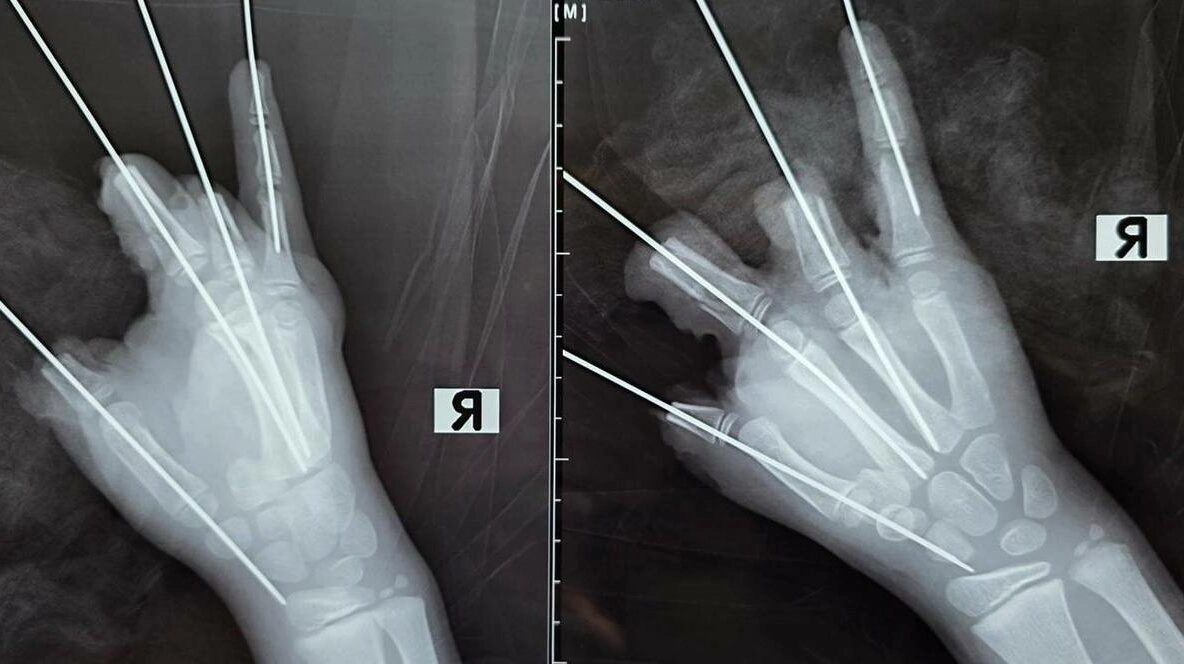

Врачи Педиатрического университета прооперировали ребёнка, у которого 11 февраля в руке взорвалась петарда, оторвав четыре пальца. Медики боролись за каждый сантиметр кисти мальчика. О результатах вмешательства рассказали в телеграм-канале СПбГПМУ.

Инцидент произошёл в Приозерском районе Ленобласти. Скорая помощь доставила пострадавшего в клинику Педиатрического университета, где его незамедлительно поместили в операционную. Хирурги работали пять 5 часов.

«Мы постарались сохранить максимально возможный объём тканей. К сожалению, повреждения были очень серьёзными, многие мягкие ткани были утрачены. При такой травме реконструировать конечность не представлялось возможным», – рассказал детский микрохирург Антон Волков.

Сейчас мальчик находится в реанимации. Медики отмечают, что в ближайшие несколько суток возможна некротизация части тканей кисти — это характерно для подобных травм.

Заведующий микрохирургическим отделением клиники Педиатрического университета Юрий Махин подчеркнул, что медики борются за каждый сантиметр тканей, который можно сохранить.